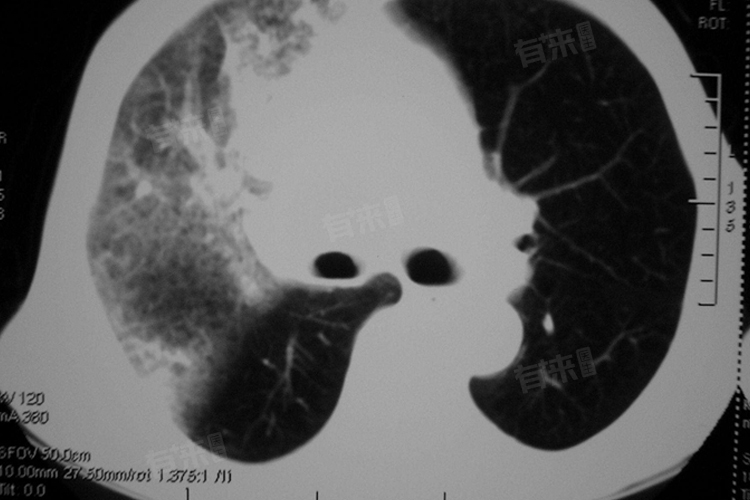

- 如果外伤比较严重,导致肺部大面积挫伤或裂伤,此时肺出血往往难以自愈,且可能伴随大量失血、呼吸困难等严重症状,需要及时就医进行救治。由肺炎、肺结核、肺癌、支气管扩张等疾病引起的肺出血,通常不能自愈。这些疾病往往需要针对原发病进行治疗,如抗感染、抗结核、抗肿瘤等,同时还需要配合止血治疗,以防止病情进一步恶化。如果肺出血同时伴有其他并发症,如气胸、胸腔积液等,也需要及时就医进行治疗,以避免病情复杂化。